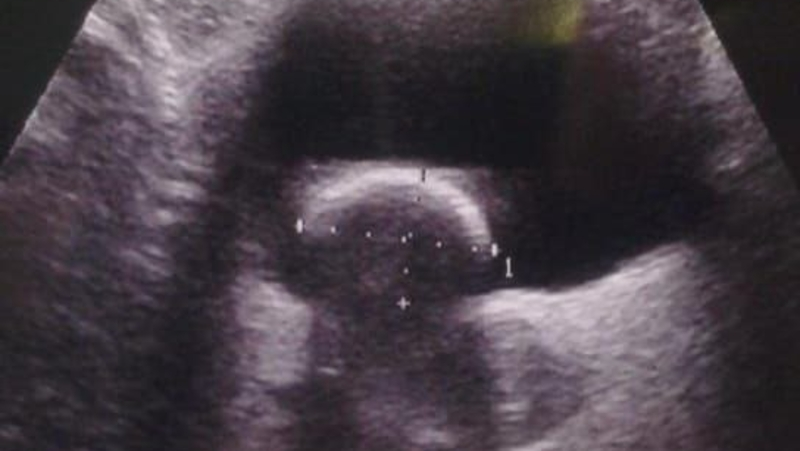

Образование крупных камней у двухлетних детей — очень редкое явление. Но именно эта беда и постигла маленькую ставропольчанку. Камень размером 2,5x2 см обнаружила в мочевом пузыре ребёнка завотделением УЗИ городской больницы скорой помощи Ставрополя Инна Стригина. Медлить было нельзя, и за дело взялись урологи.